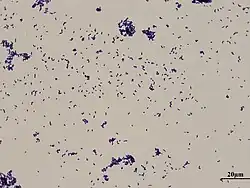

| Gram stain of Corynebacterium xerosis | |

Corynebacterium xerosis is a gram-positive, rod-shaped bacterium in the genus Corynebacterium. Although it is frequently a harmless commensal organism living on the skin and in the mucous membranes, C. xerosis is also a clinically relevant opportunistic pathogen that has been attributed to many different infections in animals and humans.[1][2] However, its actual prominence in human medicine is up for debate due to early difficulties distinguishing it from other Corynebacterium species in clinical isolates.